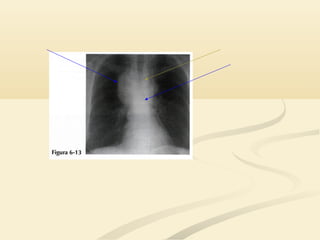

 El signo de la silueta puede ser engañoso en una placa pocoEl signo de la silueta puede ser engañoso en una placa poco

penetrada.penetrada.

 Si no puedes ver la columna a través del corazón, la placa tieneSi no puedes ver la columna a través del corazón, la placa tiene

una penetración insuficiente y el signo de la silueta puede induciruna penetración insuficiente y el signo de la silueta puede inducir

a error.a error.

 El borde cardíaco derecho se superpone a la columna y no haceEl borde cardíaco derecho se superpone a la columna y no hace

prominencia en el pulmón derecho; la densidad de hueso de laprominencia en el pulmón derecho; la densidad de hueso de la

columna oculta la interfase pulmón/corazóncolumna oculta la interfase pulmón/corazón

OJO!!!!!OJO!!!!!  El signode la silueta puede ser engañoso en una placa pocoEl signo de la silueta puede ser engañoso en una placa poco penetrada.penetrada.  Si no puedes ver la columna a través del corazón, la placa tieneSi no puedes ver la columna a través del corazón, la placa tiene una penetración insuficiente y el signo de la silueta puede induciruna penetración insuficiente y el signo de la silueta puede inducir a error.a error.  El borde cardíaco derecho se superpone a la columna y no haceEl borde cardíaco derecho se superpone a la columna y no hace prominencia en el pulmón derecho; la densidad de hueso de laprominencia en el pulmón derecho; la densidad de hueso de la columna oculta la interfase pulmón/corazóncolumna oculta la interfase pulmón/corazón